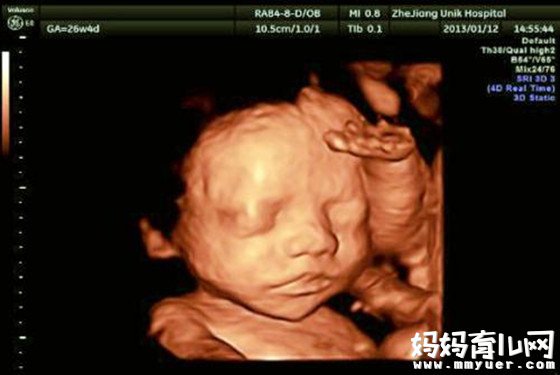

怀孕5个月胎儿图发育详情